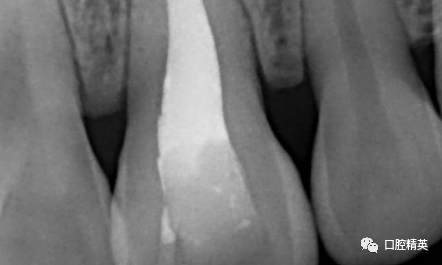

CBCT检查发现21内吸收,已做根充。根尖周可见约10mm*7mm*7mm范围低密度影像,近11,22根尖区。边界清楚。可见超充药物,查看病历曾使用碘仿和VITAPEX。

考虑21慢性根尖囊肿。拟定行囊肿切除+根尖切除倒充术。详细交代可能出现并发症,病人理解同意手术治疗。延期进行牙齿美白和美容性修复。完善术前检查,择期手术。